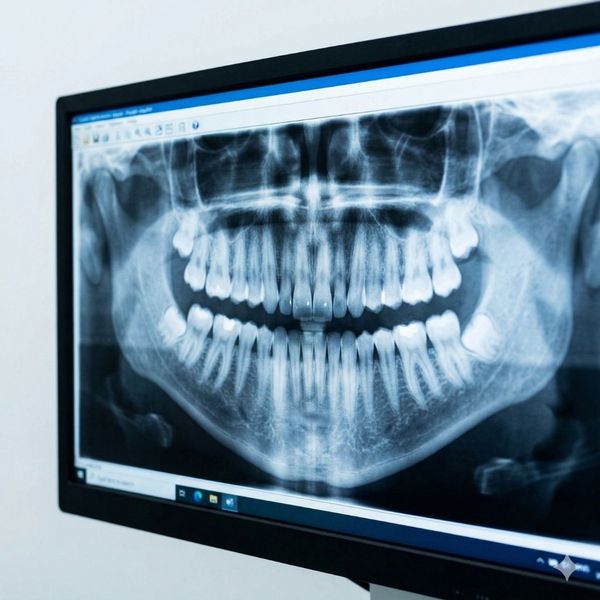

A full mouth reconstruction is a personalized series of treatments designed to rebuild or replace all the teeth in your upper and lower arches. This isn't a one-size-fits-all procedure; instead, we carefully evaluate your unique bite, jaw alignment, and gum health. By combining restorative and cosmetic techniques, we can address complex issues like severe decay, trauma, or long-term wear from grinding.

One of the most effective ways we restore strength to damaged teeth is through the use of crowns. These custom-fitted caps are designed to protect weakened structures while looking completely natural. If you have been searching for a dentist near me who specializes in durable restorations, you’ll find that high-quality crowns are often the cornerstone of a stable, long-lasting, and beautiful smile.

For those facing significant tooth loss, our dental clinic in Kissimmee, FL, offers advanced solutions like dental implants and bridges. These options do more than just fill gaps; they preserve your jawbone and prevent neighboring teeth from shifting. By integrating these treatments into your reconstruction plan, we ensure that your new smile is as functional as it is attractive, allowing you to eat and speak with ease.